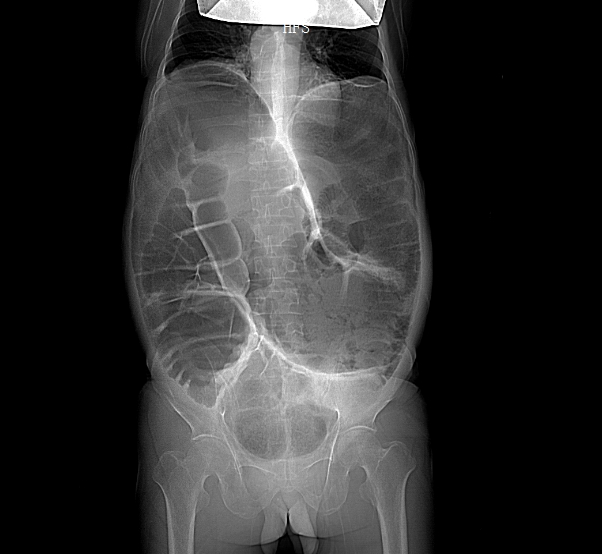

考虑到甘先生身体虚弱,无法配合完成钡灌肠大肠造影,胃肠外科·小儿外科团队给他安排了腹部 CT、DR 和肠镜检查。

结果一出来,答案清晰了:他的升结肠、横结肠显著扩张,像被吹大的气球,胀得异常粗大;可远端的结肠和直肠,却明显狭窄。